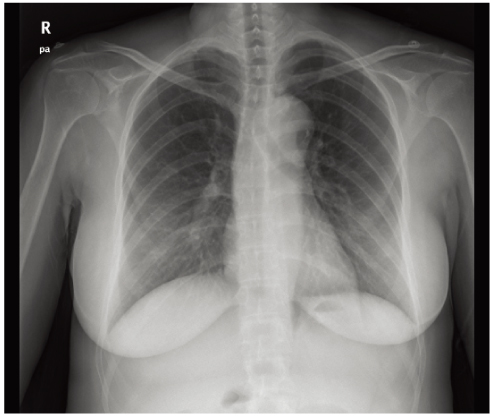

Unexpected acute aortic dissection after elective cesarean section delivery: Report of a case and review of the literature

- Acute aortic dissection may indeed be a rare complication of pregnancy, and the majority of aortic dissections usually occur during the third trimester of pregnancy. Most aortic dissections occur as a result of systemic hypertension or connective tissue disorders. Without any treatment, more than 50% of patients die within the initial 48 hours, and the 3-month mortality rate is as high as 90%. Because the pain in puerperal women is uncertain and difficult to discriminate from physiologic pain, the diagnosis of aortic dissection is complex and requires a high index of suspicion. We experienced a case of unexpected acute aortic dissection that occurred after elective cesarean section delivery in a young woman without any known risk factors. This case of aortic dissection was managed medically. In postpartum patients complaining of chest pain, the suspicion of aortic dissection is important for prompt diagnosis and better prognosis.

Figure